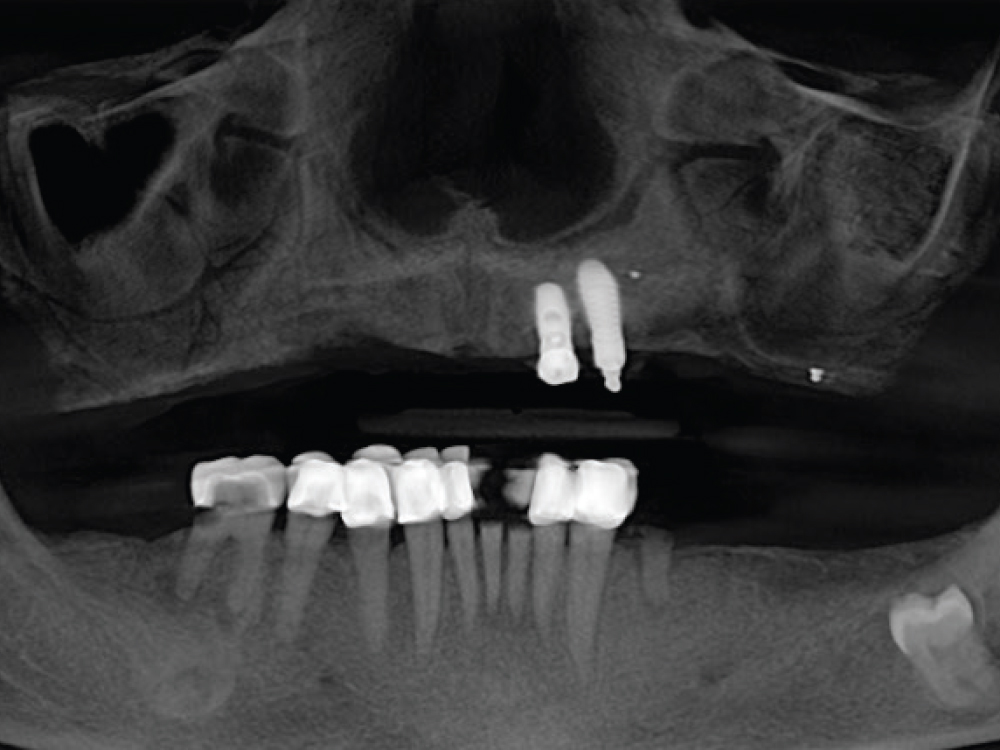

This panoramic X-ray shows traditional maxillary and mandibular All-on-4® hybrid prostheses with milled titanium bars supporting a screw-retained hybrid denture.

This preoperative X-ray shows the terminal mandibular dentition and a maxillary overdenture retained by two implants

Figure 1: This preoperative X-ray shows the terminal mandibular dentition and a maxillary overdenture retained by two implants.